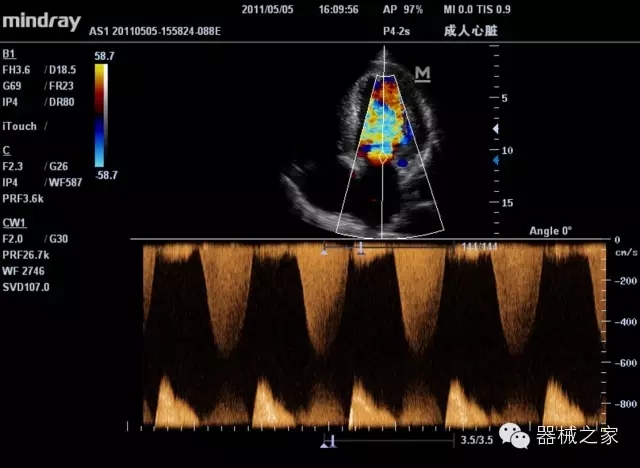

經典產品:M7(星鉆)

臨床圖片賞析

產品特點

·裝載有采用Multi-Core多核處理的非嵌入式平臺,成像效率大大提高,并且能夠給用戶帶來高速、多任務并行信號處理體驗;

·優(yōu)秀的圖像效果、強大的功能體驗、豐富的探頭選擇、合理的便攜式設計,全中文顯示及病人管理界面,使得M7在任何場合、任何時候都能快速響應更好的心血管、腹部、婦產、小器官等常規(guī)超聲檢查以及肌骨、神經、顱腦、術中等新興領域的使用需求;

8倍波束并行處理系統(tǒng)

·在便攜式緊湊平臺上采用更多倍波束并行接收信號處理模式,無論二維還是彩色血流圖像狀態(tài)下,擁有更靈敏的回波頻移捕獲能力,大大提高時間分辨率,尤其使得心血管表現更為突出;

PSHI?寬帶頻移諧波技術

·在普通組織諧波的基礎上,通過精確控制的波束形成器,發(fā)射兩組具有相位偏差反向的信號,并采用并行信號處理,數字化合成并采樣回波信號,在高靈敏度的濾波器的處理過程中獲取更純凈的諧波信號,使圖像具有更加出眾的細節(jié)分辨率;

iClear®+iBeam?

·智能化按線復合多角度獲取聲束的原始信號,配合智能化的斑點噪聲識別及控制處理技術,整體提高組織結構細節(jié)分辨率,任何時候都能快速響應,更好的滿足心血管的使用需求;

支持全新3T工藝探頭群

·包括探頭材料、結構設計、加工工藝三方面的革新技術給圖像帶來品質的飛躍;

CFDA注冊證編號

·粵食藥監(jiān)械(準)字20132230475